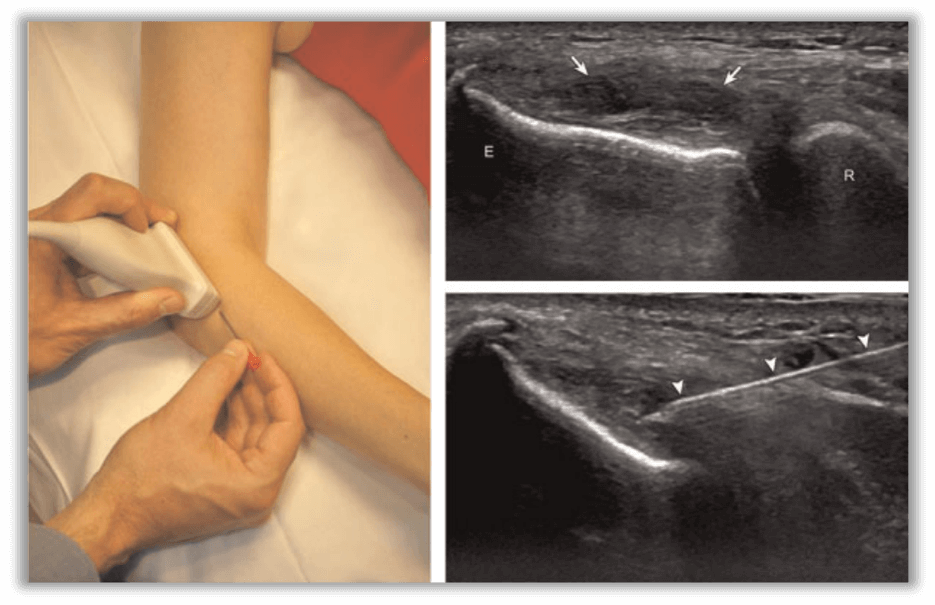

Figure 3 - Procedural set-up and ultrasound image of percutaneous needle tenotomy for elbow common extensor tendinosis (Tennis Elbow) (Chiavaras et al., 2013)